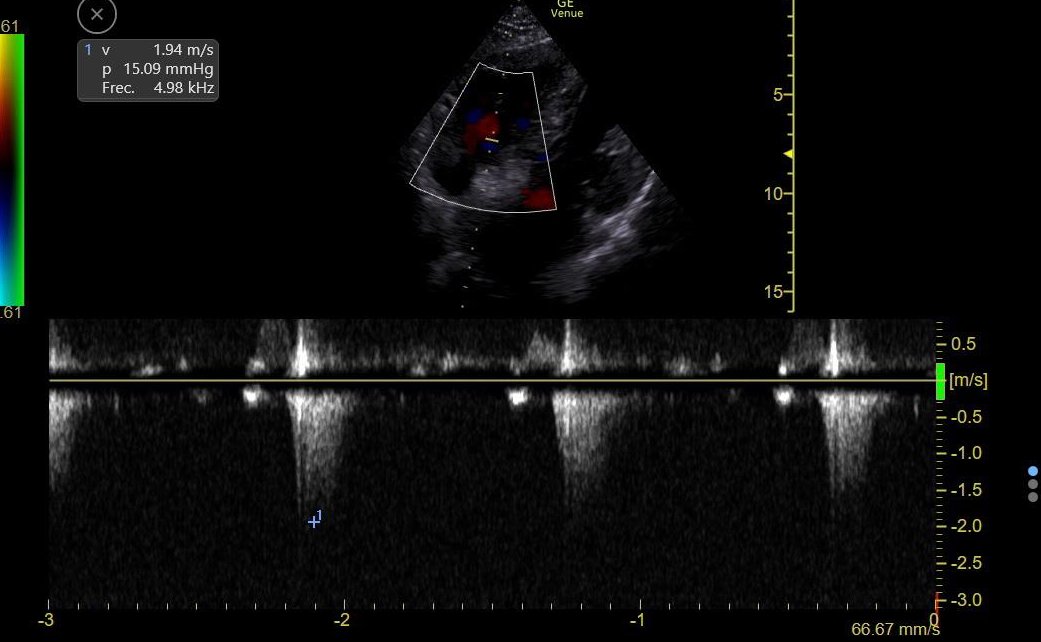

Only subxiphoid window was available:

LV and RV hypertrophy, Moderately ⬇️ LVEF, normal RV function, No tamponade, No RV Failure

These findings strongly argue against:

🔷 Right HF / PAH

🔷 Obstruction (Tamponade, PE)